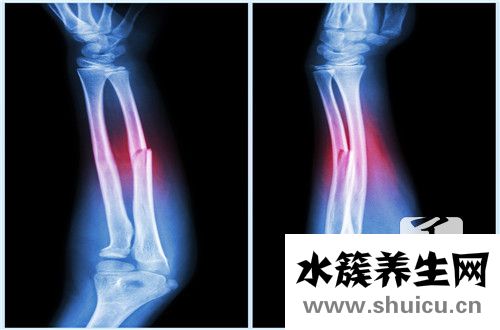

尺骨和radius骨是人体上臂骨骼的一部分。 运输较为重物时,每个人都有可能发生尺骨骨折和radius骨骨折等情况。 这种情况对身体有很大的影响。 较为 较为做居中中的许多事情很不方便。 为了应对尺...